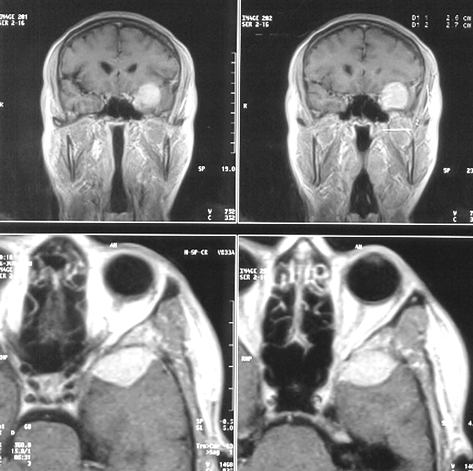

Менингиомы площадки основной кости (рис. 4)

Рисунок 4. Менингиома площадки основной кости. МРТ, Т2-взвешенные изображения, КТ (слева внизу) с контрастным усилением

Менингиомы бугорка турецкого седла

Исходят из ТМО бугорка турецкого седла, хиазмальной борозды (рис. 5). Они имеют тенденцию к распространению кзади — ретрохиазмально, кпереди — на площадку основной кости. В эту же группу обычно включают менингиомы диафрагмы турецкого седла, встречающиеся редко и характеризующиеся отсутствием гиперостоза.

Рисунок 5. Менингиома бугорка турецкого седла. МРТ, Т1 (вверху) и Т2 (внизу) — взвешенные изображения